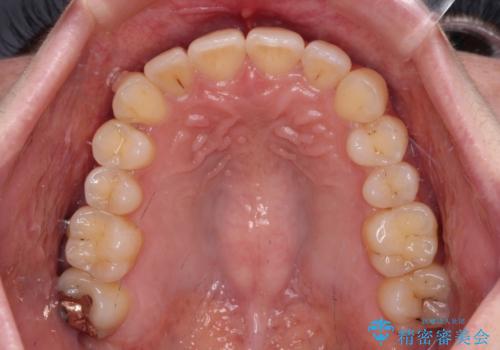

- 前歯のデコボコと強い咬みしめを気にして来院された患者様です。

インビザラインを用いて、前歯の叢生を解消するとともに、ディープバイトを改善していくこととしました。

海外へ転居する予定があったため、1日22時間以上の装着時間をしっかりと守っていただき、予定期間よりも早く、思っていた以上にきれいに仕上げることができました。